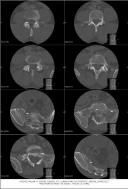

Nuclear Scan Images of Lower Torso & Lower Legs

These images were captured in order to determine why Liam’s bones broke so easily playing a video game and to also determine if there

was any Osteomyelitis. This is the diagnosis report from the scan. "There is mild increased activity noted in the lateral side of the left

ankle. However the patient does have a cast on the left leg. This uptake can be secondary to either inflammatory or infectious change within

either the skin or adjacent bone." Various contrast were used to enhance image details. The last images reminds one of the Shroud of Turin.

Hummm, makes one wonder... ;-)